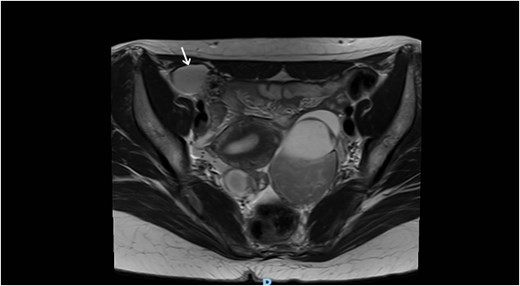

Laboratory studies, including complete blood count and comprehensive metabolic panel, were within normal limits. Initial ultrasonography (US) revealed an oblong cystic lesion with fine septations, measuring 6.5 × 3 cm, extending through the right inguinal canal into the labium majus (Figs 1 and 2). Subsequent pelvic magnetic resonance imaging (MRI) corroborated these findings, demonstrating a right lower abdominal cystic lesion with thin septations extending to the inguinal region, showing low T1 and high T2 signal intensity, measuring ~7 × 3.5 cm (Figs 3 and 4). No evidence of bowel or omental herniation was observed, suggesting canal of Nuck hydrocele.

Axial MRI view of the pelvis, showing the extension of the cyst into the right inguinal canal with no bowel or omental herniation (arrow).